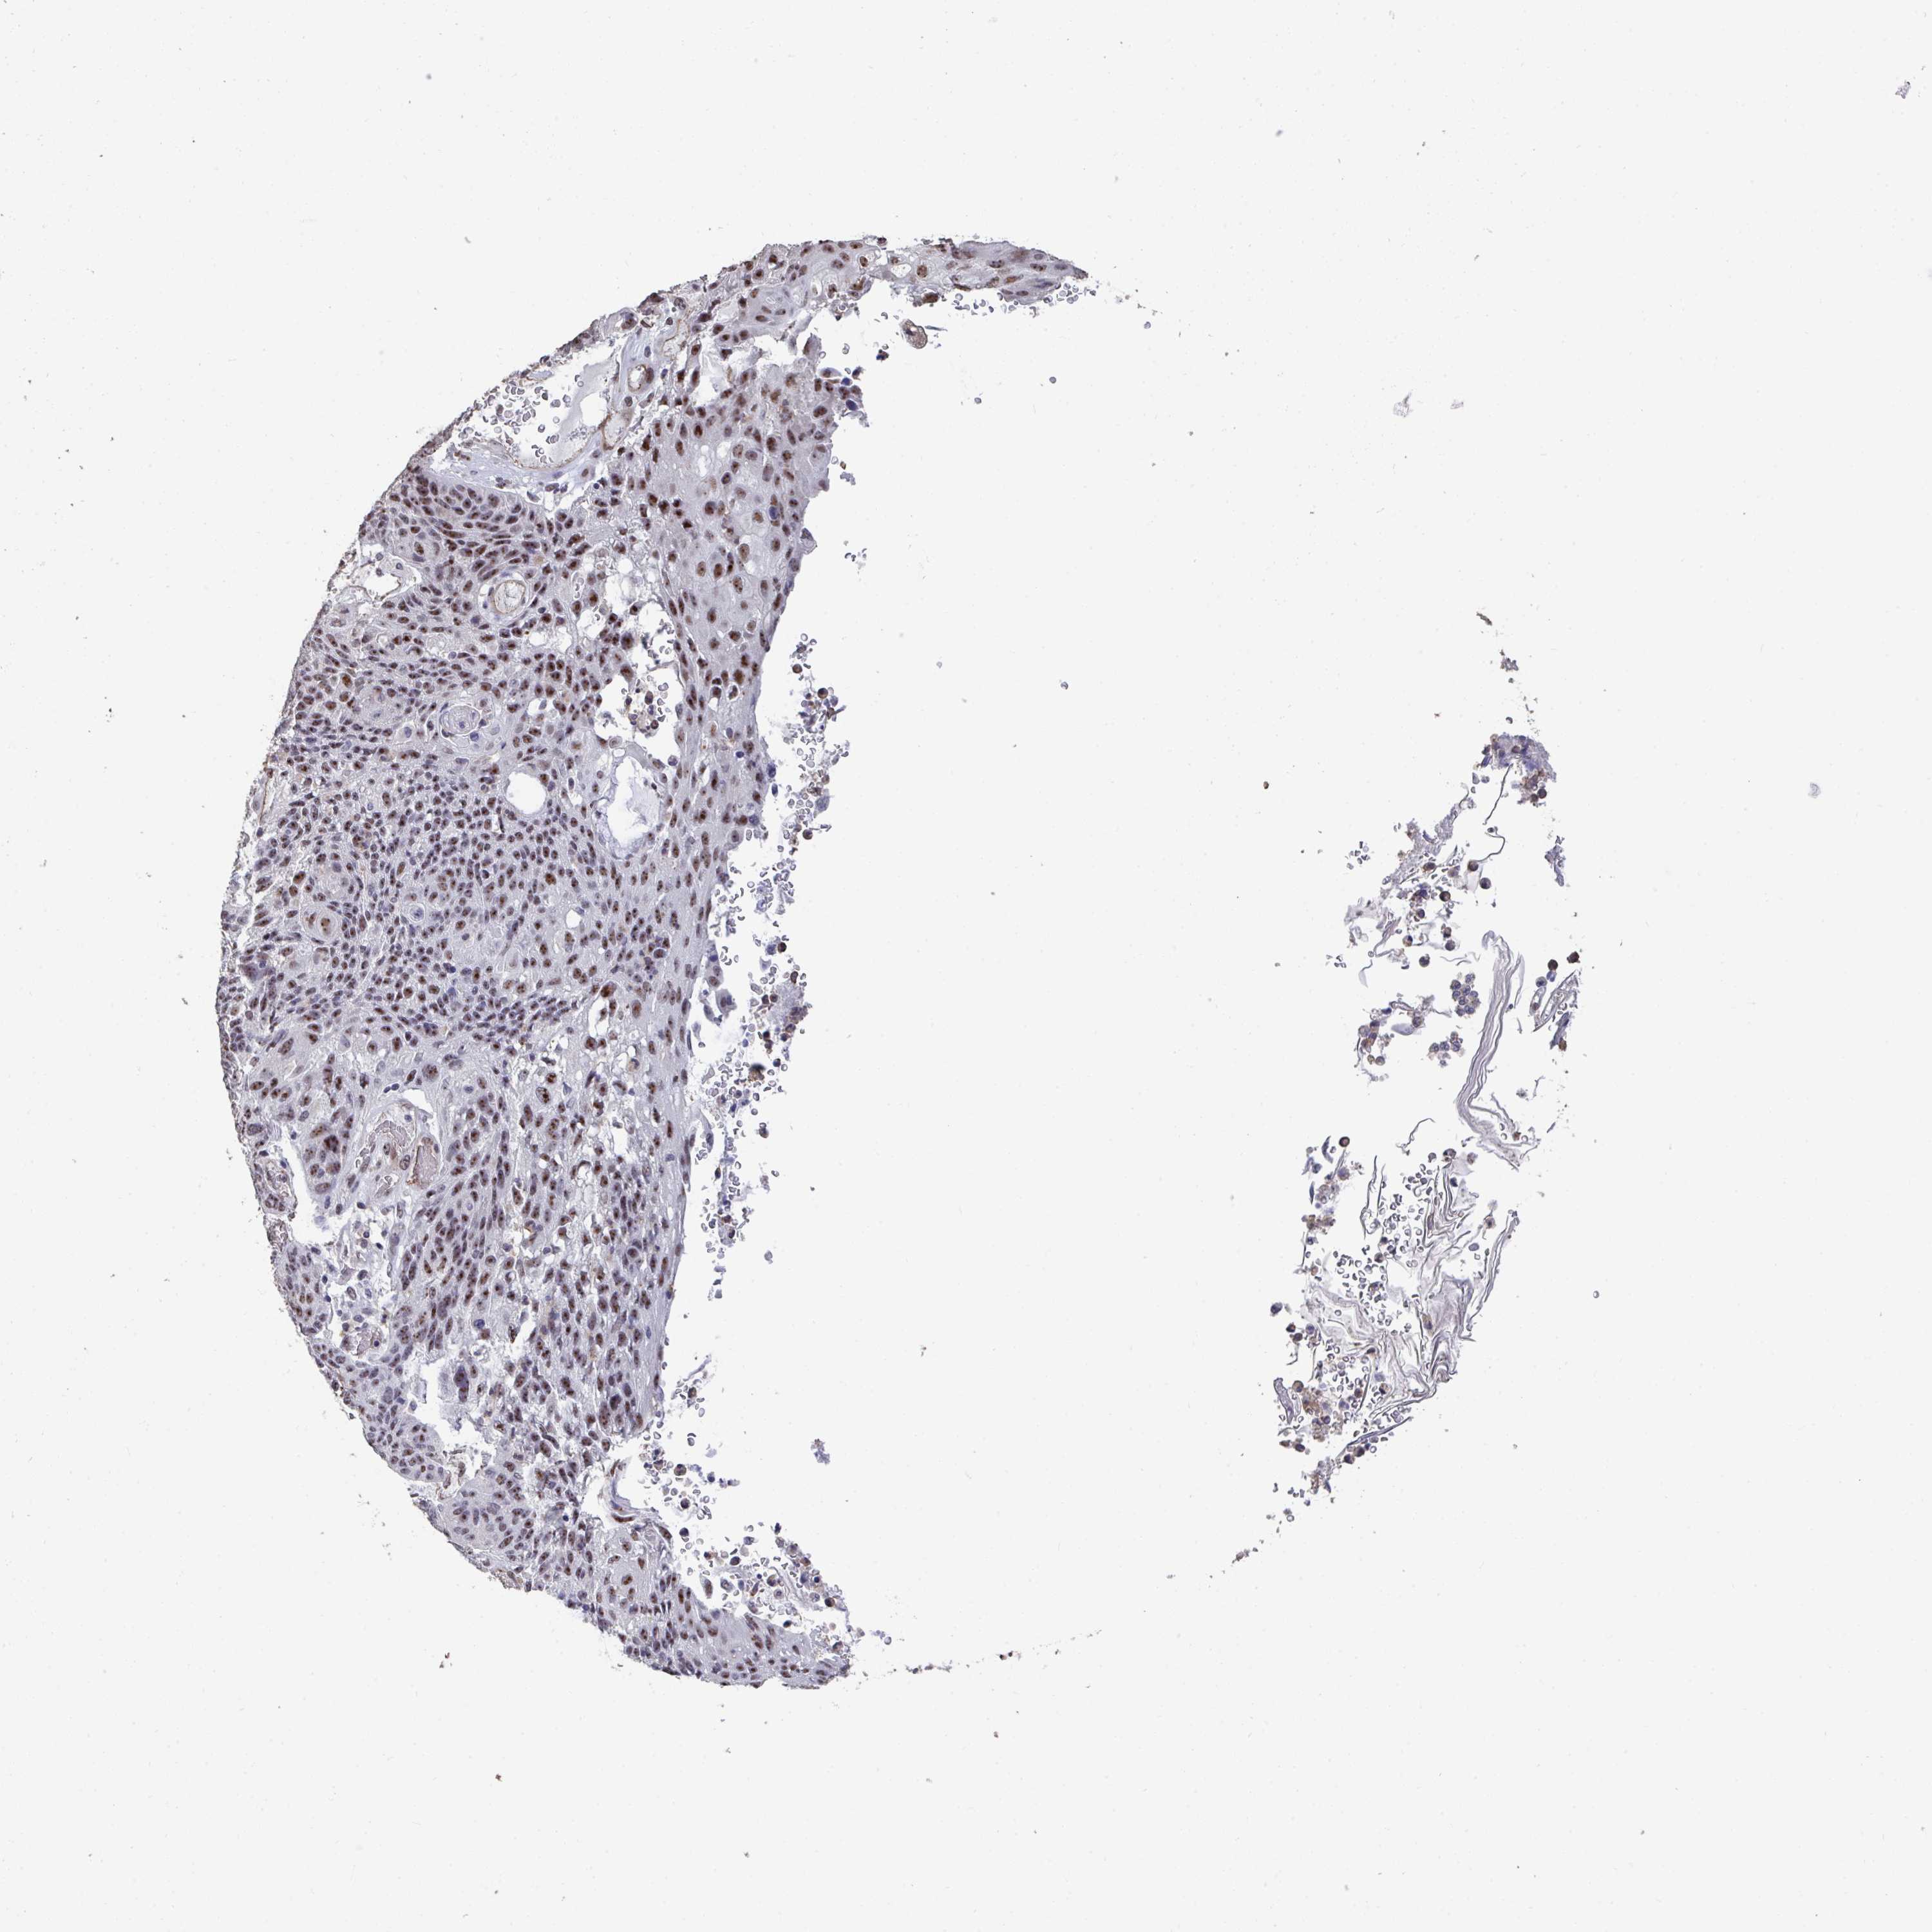

LUNG ADENOCARCINOMA (VALIDATION) - Interactive survival scatter ploti

The Survival Scatter plot shows the clinical status (i.e. dead or alive) for all individuals in the patient cohort, based on the same data that underlies the corresponding Kaplan-Meier plots. Patients that are alive at last time for follow-up are shown in blue and patients who have died during the study are shown in red.

The x-axis shows the expression levels (FPKM) of the investigated gene in the tumor tissue at the time of diagnosis. The y-axis shows the follow-up time after diagnosis (years). Both axes are complimented with kernel density curves demonstrating the data density over the axes. The top density plot shows the expression levels (FPKM) distribution among dead (red) and alive patients (blue). The right density plot shows the data density of the survived years of dead patients with high and low expression levels respectively, stratified using the cutoff indicated by the vertical dashed line through the Survival Scatter plot. This cutoff is automatically defined based on the FPKM cutoff that minimizes the p-score. The cutoff can be changed by dragging the vertical line or by entering a cutoff value in the square labeled "Current cut-off".

Under the Survival Scatter plot the p-score landscape (black curve; left axis) is shown together with dead median separation (red curve; right axis). Dead median separation is the difference in median mRNA expression between patients who have died with high and low expression, respectively. It is calculated as follows: median FPKM expression of dead patients with high expression - median FPKM expression of dead patients with low expression. This is intended to aid the user in visually exploring custom cutoffs and the associated p-scores and dead median separation.

Individual patient data is displayed and can be filtered by clicking on one or more of the category buttons on the top of the page. Categories describing expression level and patient information include: high, low, alive, dead, female, male and tumor stages. The scale of the x-axis can be toggled between linear and log-scale by clicking on the "x log" button. Mouse-over function shows TCGA ID, patient information and mRNA expression (FPKM) for each patient.

& Survival analysisi

Kaplan-Meier plots summarize results from analysis of correlation between mRNA expression level and patient survival. Patients were divided based on level of expression into one of the two groups "low" (under cut off) or "high" (over cut off). X-axis shows time for survival (years) and y-axis shows the probability of survival, where 1.0 corresponds to 100 percent.

SENP3 is not prognostic in Lung Adenocarcinoma (validation)

: 36.4

Average pTPM 35.5

Number of samples 105